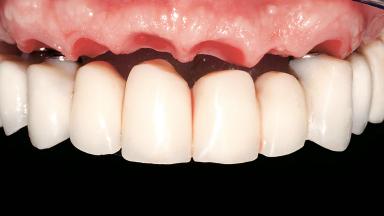

A 63-year-old male patient was referred for a consultation and treatment of partial edentulism in the maxilla. The patient presented with residual anterior teeth and declined a partial removable prosthesis. He reported that the maxillary posterior teeth had been extracted due to mobility and periodontal disease two months before the consultation. The patient’s chief complaint was that his residual maxillary teeth were mobile and that he was unable to chew. The patient’s desire was a stable and comfortable fixed maxillary rehabilitation. The patient was a light smoker (fewer than 10 cigarettes/ day), and his medical history was without significant findings. He was not on any regular medication at the time of consultation. The extraoral examination revealed a normal physiognomy with a correct distribution of the facial thirds. The patient presented a low lip line, and the transition line between teeth and soft tissues was not exposed during a forced smile.

| Abutment Type | CAD/CAM |

| Prosthesis Type | FDP |